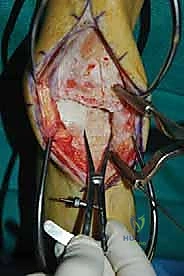

الغوص العميق في جراحة الطعم الخيفي الهيكلي (Structural Allograft Reconstruction)

يهدف هذا الإجراء العبقري إلى استبدال الغضروف والعظم التالفين والميتين بنسيج سليم تماماً مأخوذ من متبرع متوفى (طعم خيفي - Allograft). هذا الطعم يتم تعقيمه وحفظه في بنوك الأنسجة العالمية وفقاً لأعلى المعايير الطبية الصارمة لضمان خلوه من أي أمراض معدية والحفاظ على حيوية الخلايا الغضروفية.

- الترميم التشريحي الحقيقي: يسمح باستعادة الشكل الهندسي الدقيق لعظم الكاحل، بما في ذلك المنحنيات المعقدة لكتف التالوس.

- توفير غضروف طبيعي (Hyaline Cartilage): الغضروف المزروع هو غضروف زجاجي طبيعي،